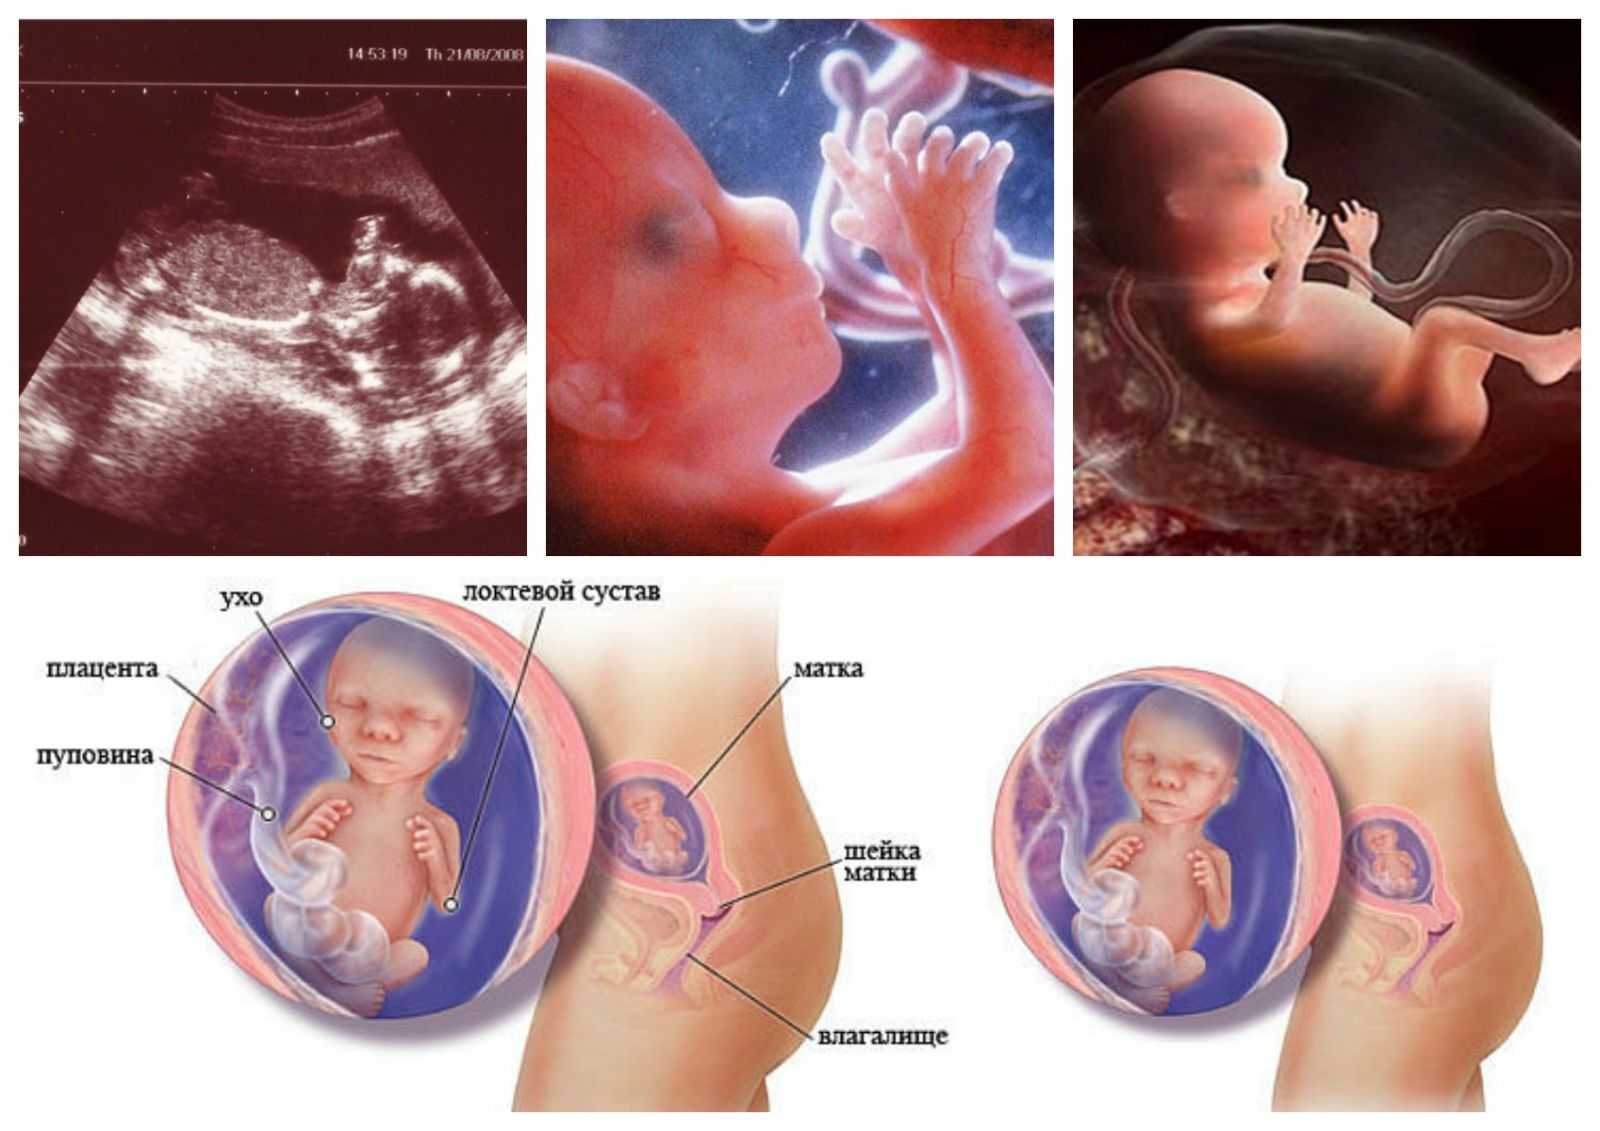

Расположение плода на 15-й неделе беременности: фотографии и иллюстрации